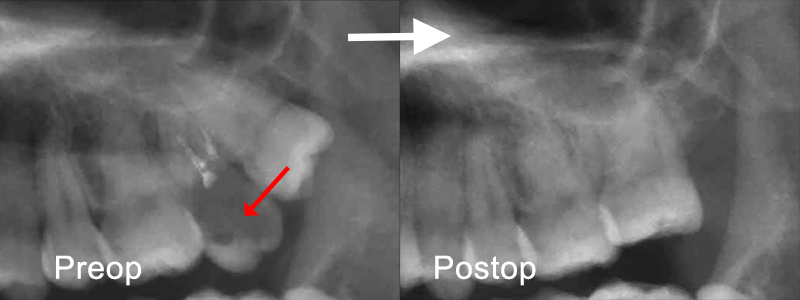

年配者と若者世代では歯科再建治療に対するアプローチはまったく異なる。 生存年数や活動年数が中高年世代と20代の世代では30年以上の実質差があり、長期的な戦略としてはエナメル質の保存、歯髄の保存が最優先し、生体としての自己再生能を維持すべき治療が推奨される。 以下の症例は治療開始時24歳で下顎第一大臼歯は歯冠崩壊が顕著であるも、歯根部はかろうじてカリエス進行から免れるが、第二大臼歯は完全に歯根も腐食して保存不能。

世代が上がれば後方の90度変位した埋伏智歯の移植利用を考えるが歯髄失活は免れないため、困難な矯正であるが萌出間もない大臼歯として今後を託せる生活歯のまま保存する。 矯正用のアンカースクリューと各種装置を智歯に接着させ、移動の各段階で交換しながら抜歯した第二大臼歯部に誘導する。 第一大臼歯は保存治療後ジルコニアセラミック冠で歯冠修復し約7年経過。 治療期間は 2017/12~2019/03

前方大臼歯抜歯時に矯正用アンカーを歯槽骨にねじ込み、引張用のアタッチメントを智歯歯冠に接着